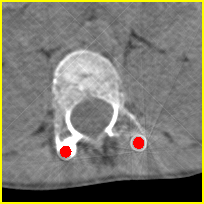

Visual comparison. As shown in Fig. 5, metallic implants such as spinal rods and hip prosthesis cause severe streaky artifacts and metal shadows, which obscure bone structures around them. cGan-CT cannot recover image intensity correctly for both cases. Sinogram domain or dual-domain methods perform much better than cGan-CT. LI, NMAR, and CNNMAR introduce strong secondary artifacts and distort the whole images. In NMAR images, there are fake bone structures around the metals, which is related to segmentation error in the prior image from strong metal artifacts. The segmentation error is also visible in NMAR sinogram. CNNMAR cannot restore the correct bone structures between rods in case 1. The tissues around the metals are over-smoothed in DuDoNet because LI sinogram and image are used as inputs, and the missing information cannot be inferred later. Our model retains more structural information than DuDoNet and generates anatomically more faithful artifact-reduced images.

Visual comparison. Fig. 7 shows two clinical CT images with metal artifacts. Case 1 is with moderate metal artifacts. cGan-CT does not suppress the artifacts completely and generates some fake details. LI, NMAR, CNN-MAR remove all the artifacts but introduce new streak artifacts, which is caused by the discontinuity in the corrected sinogram. DuDoNet outputs over-smoothed sinogram, which leads to blurred tissues close to the metal implants, such as muscle and bone. Only our model can provide realistic enhanced sinogram and remove the artifacts while retaining the structure of nearby tissues. Case 2 is very challenging as the rods bring strong metal shadows and bright artifacts around the vertebra. cGan-CT recovers the shape of vertebra but changes the overall image intensity. Other sinogram inpainting methods fail as the soft tissue and bone near the rods are heavily distorted. Our model removes part of the dark bands and reproduces correct anatomical structures around the rods.